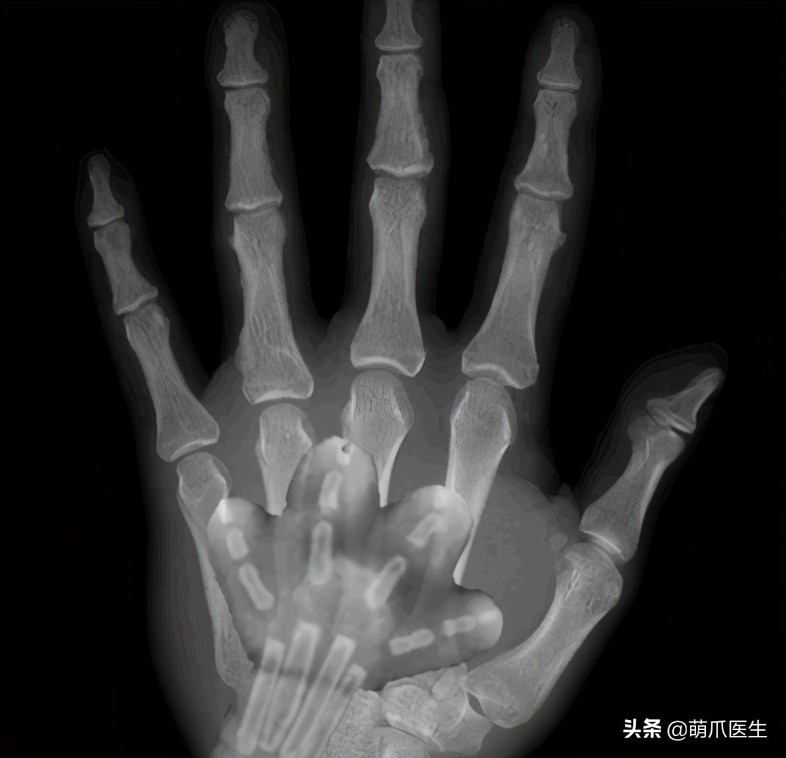

但可以明确的是,猫咪骨骼发育完全时,爪爪的X光片绝对就长这样:

或许,真的是岁月夺走了猫爪卖萌的权力吧……